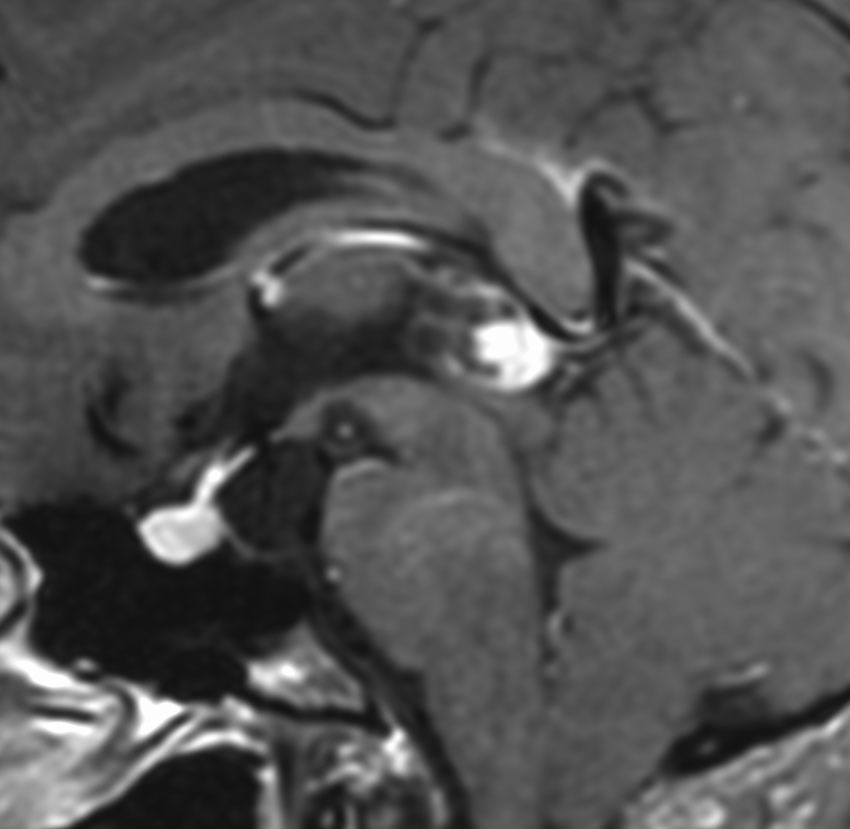

これも偶然発見された無症状の女性の小さい松果体細胞腫ですが,ほとんど実質性でのう胞がありません。右はCISSという画像です。中脳の視蓋は圧迫されて変形していますが,中脳水道がまだ閉塞していないのがよくわかります。